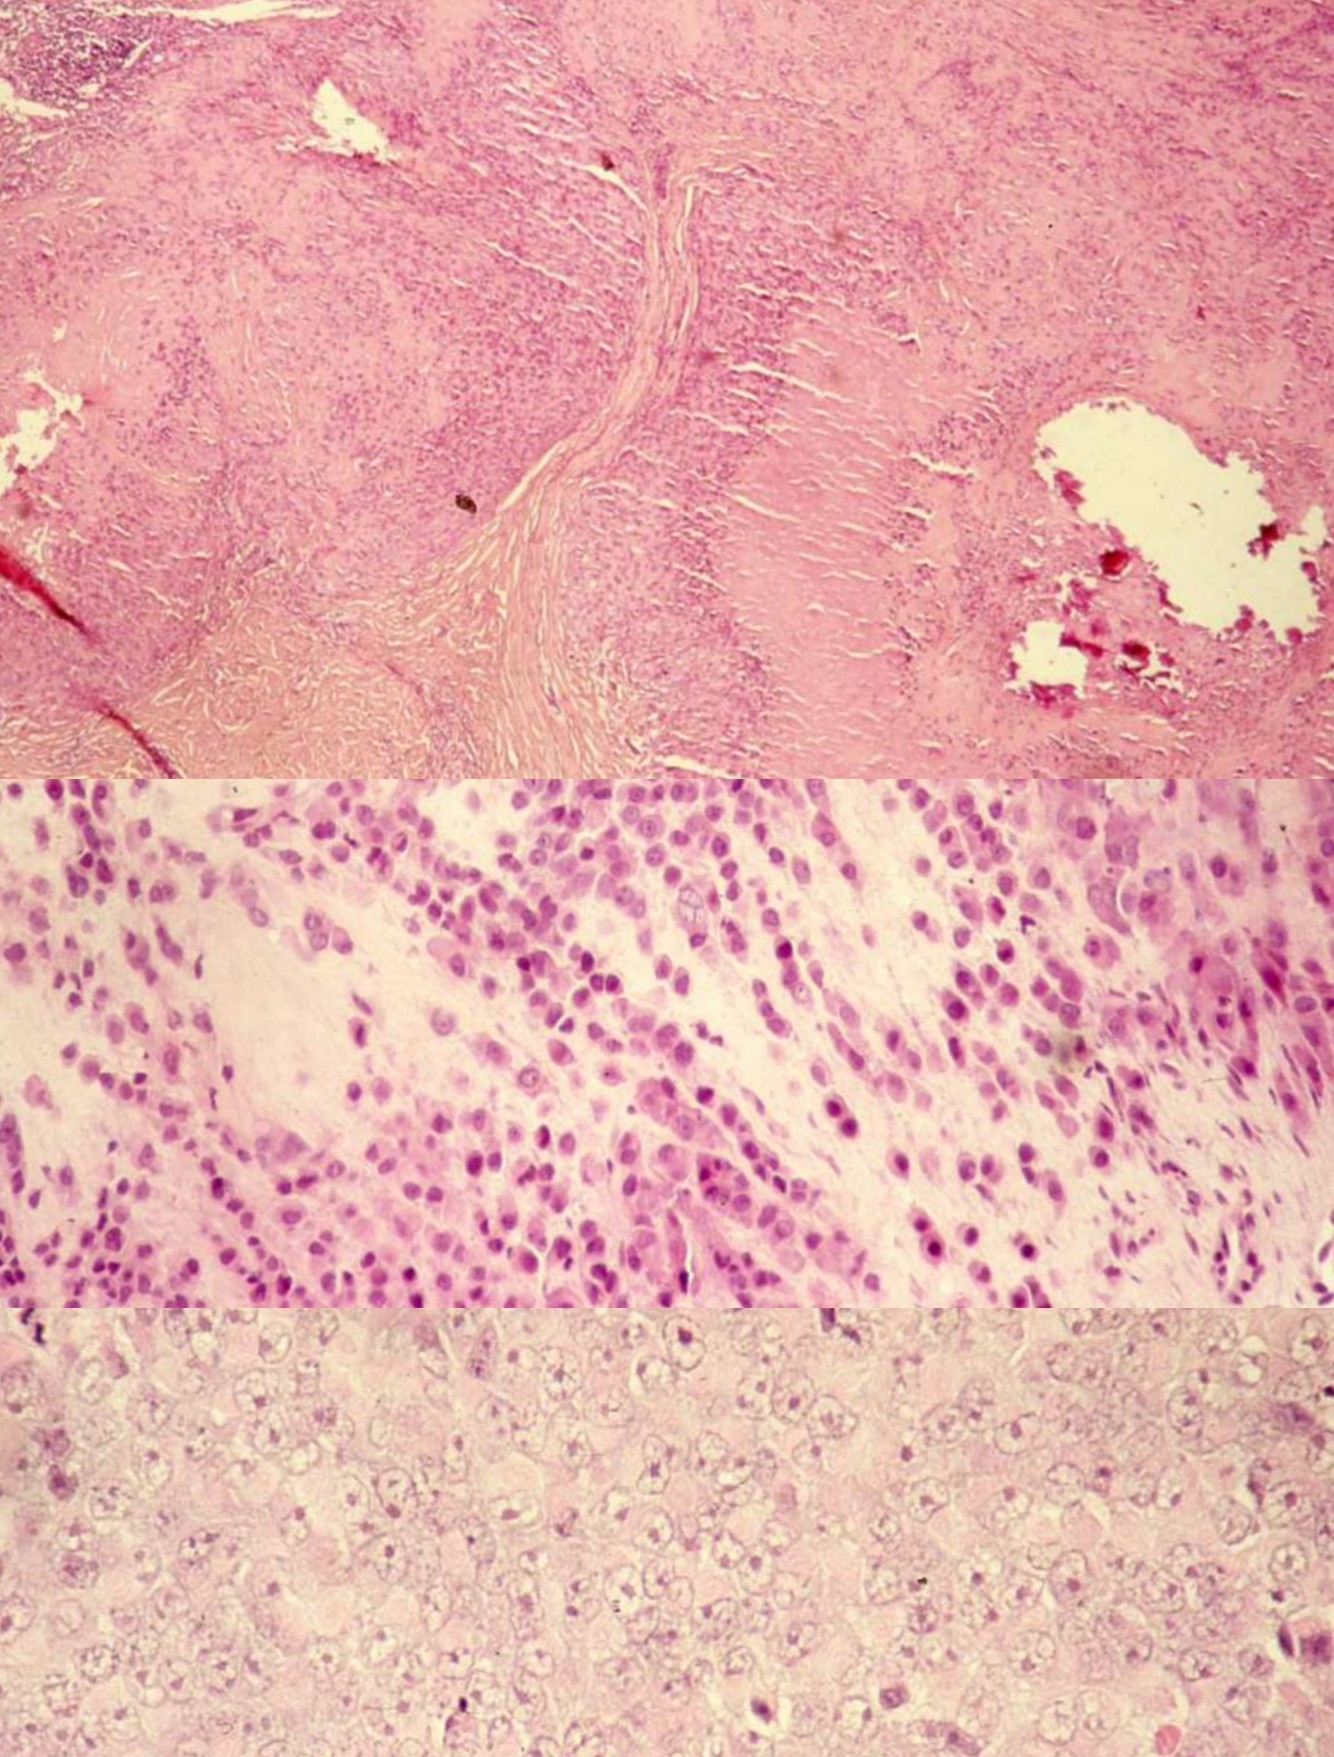

SYNOVIAL SARCOMA

• Genetics:

• t(X;18)(p11.2; q11): SYT-SSX1 genes in 90%; can detect via PCR

• t(X;18)(p11.21;q11): SYT-SSX2 fusion genes; variants can be detected by optimizing RT-PC

• p16INK4A gene deletion in 74%

• High expression of EZH2 helps to distinguish poorly differentiated synovial sarcoma from monophasic and biphasic subtypes

• Clinical:

• deep seated mass present for years around large joints (80% in knee and ankle) in young adults (age 20-40), M > F

• 10-15% metastasize to lung and pleura, bone, regional nodes

• Minute (< 1 cm) tumors of hands and feet, F > M, median 29 yo

• Gross:

• Well circumscribed, firm, gray-pink

• Focal calcifications on Xray

• Histology:

• Biphasic, monophasic or undifferentiated

• Biphasic have spindle cells resembling synoviocytes and plump epithelial cells forming glands/cords

• Monophasic lack the epithelial cells

• Spindle cells are arranged in plump fascicles with hyalinization and distinct lobulation accompanied by mast cells, occasional osseous or cartilaginous metaplasia, focal whorling

• +/- hemangiopericytomatous vascular pattern

• Monophasic much more common than biphasic.

• Stains

• Positive: Keratin, EMA, S100, bcl2, TLE1, CD99, vimentin, CEA, CD57, E-cadherin (50%), S100 (30-40%), c-kit , nuclear beta-catenin

• Negative: CD34, desmin, myogenin, h-caldesmon, CD141, WT1, FLI-1

• Mucin - spindle cell areas, PAS positive - epithelium, reticulin highlights biphasic pattern

• Poor prognostic factors: high histologic grade (based on MIB1 index and necrosis), SYT-SSX1 vs. SYT-SSX2 gene fusion

MALIGNANT PERIPHERAL NERVE SHEATH TUMOR

• S100 negative except for epithelioid MPNST.

• Definitive diagnosis of MPNST: history of neurofibromatosis, origin from major nerve trunk, areas of a benign PNST

• Variants of MPNST: Triton tumor, MPNST with angiosarcoma, epithelioid MPNST